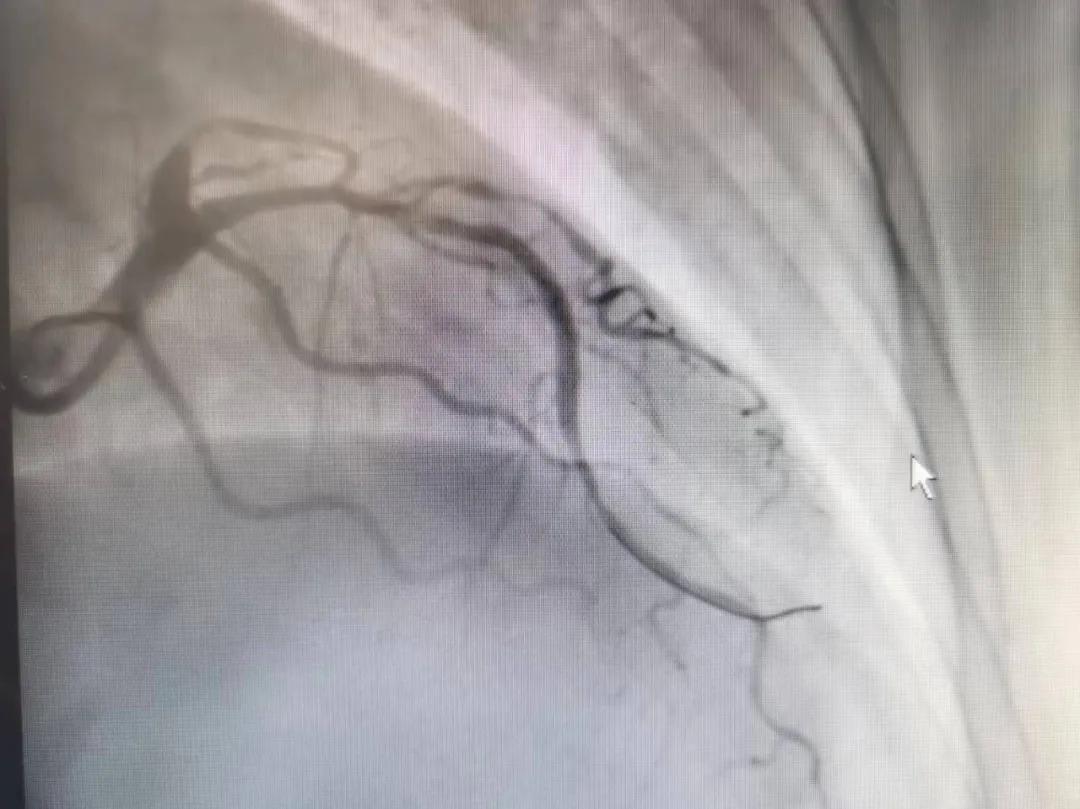

病人是位六十多歲的女性患者,有長期高血壓病史,1個月前開始出現(xiàn)胸悶胸痛,口服藥物治療效果不佳,經(jīng)朋友介紹,來到市二院心血管內(nèi)科。入院后完善冠狀動脈造影提示:前降支全程彌漫性狹窄伴鈣化,最重95%,回旋支狹窄約85%,右冠脈全程狹窄伴鈣化,最重60%。血管內(nèi)超聲顯示右冠脈開口面積3.36mm²,可見環(huán)形鈣化,考慮患者病變程度重、鈣化明顯,常規(guī)器械無法實現(xiàn)病變的良好預(yù)處理,且有很高的冠脈穿孔、血管夾層的風險。

術(shù)前

王瑾院長和李慧新主任帶領(lǐng)介入團隊充分評估,決定行前降支冠狀動脈鈣化病變旋磨術(shù),術(shù)中應(yīng)用1.5mm旋磨頭,以15萬-17萬轉(zhuǎn)/分速度共對病變旋磨3次,累計旋磨時間60秒,后復(fù)查造影示鈣化明顯減輕,為后續(xù)操作創(chuàng)造了良好條件,隨后應(yīng)用預(yù)擴張球囊、切割球囊再次處理病變,并順利植入支架1枚,復(fù)查造影顯示支架膨脹及貼壁良好,無夾層、血腫、慢血流等情況,手術(shù)順利完成。患者術(shù)后無不適,胸悶、胸痛癥狀明顯緩解,順利出院。